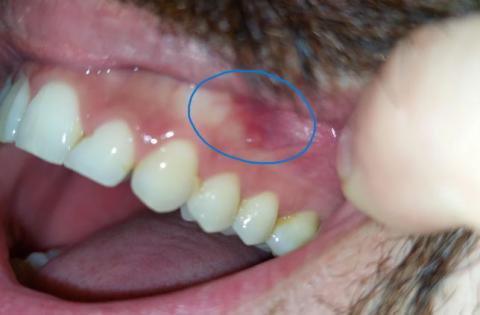

The image shows a localized red area on the gum near the side teeth, highlighted in the photo. The teeth themselves appear mostly intact, but the gum tissue in this area looks inflamed and irritated. This type of lesion is often related to local trauma, irritation, or early infection.

This condition should be monitored closely, even if pain is mild.